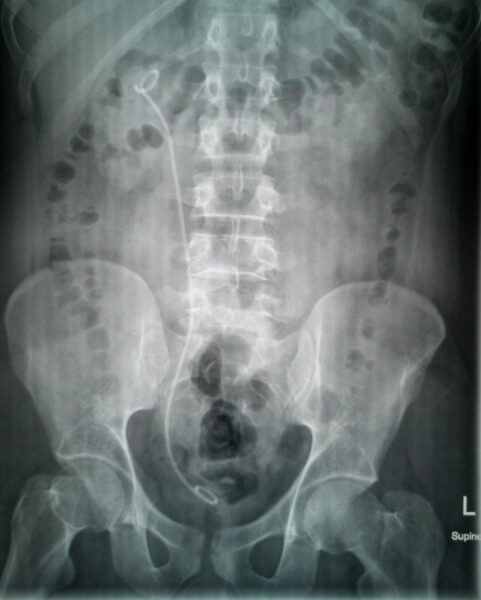

La sonde JJ est un tube souple, généralement fabriqué en polyuréthane ou en silicone, placé dans l’uretère. Sa configuration comprend :

- Extrémité supérieure : enroulée dans le rein

- Extrémité inférieure : enroulée dans la vessie

Cette conception en “double J” présente plusieurs avantages :

- Empêche la migration

- Assure une position stable

- Permet un drainage continu